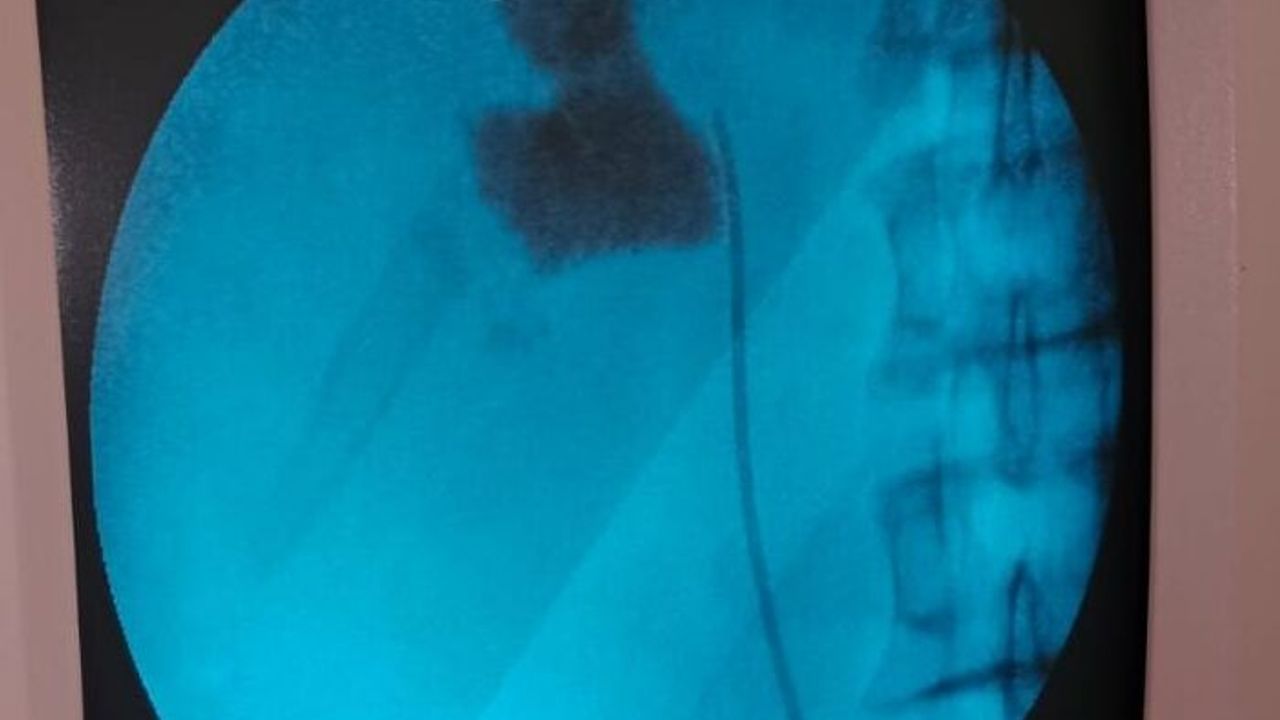

Uzm. Dr. Talip Göktaş da kontrollerde hastanın sol böbreğinde 6 santimlik taş tespit ettiklerini, kapalı böbrek taşı yöntemi PNL ile ameliyatı gerçekleştirdiklerini belirterek, "Hastamız 1 gün sonra taburcu edildi. Bu yöntemle hastalarımız açık ameliyatlara göre erken dönemde işlerine dönebiliyor ve daha konforlu bir şekilde ameliyat sürecini atlatabiliyor. 5 yıl içinde hastanemizde 50'den fazla bu tarz ameliyatları başarıyla gerçekleştirdik." ifadesini kullandı.